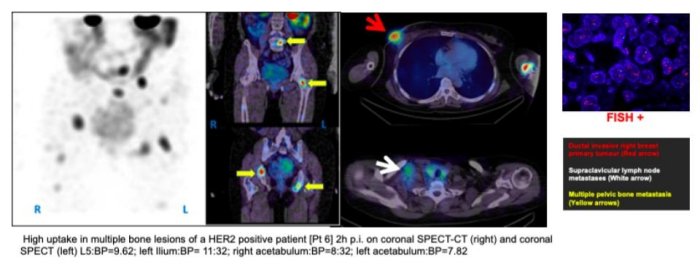

99mTc-HER-2 Imaging In Breast Cancer

Uptake of 99mTc-HER-2 was also observed in nodal and distant metastatic lesions in multiple pelvic bones and lungs of a HER2 IHC positive patient with excellent conspicuity to background. Metastatic disease was confirmed with CT scan.